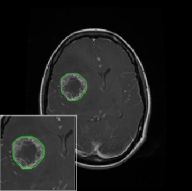

Fig. 4 displays the visual comparison results for segmenting eight brain tumor MR images between the RefLSM and three representative models: the RESLS [8765635], ALF[MA2019201], and L1 model[LIU2019193]. These images exhibit severe intensity inhomogeneity and noise attributable to inconsistent bias field and imaging equipment. The initial level set function (LSF) initialization was consistent across all models, as shown in Fig. 4 (a), which illustrates the initial placement of the zero level contour. For visual clarity, we included the ground truth in Fig. 4 (f). The segmentation outcomes from the RESLS, ALF, and L1 methods are presented in Fig. 4 (b), (c), and (d), respectively.

It is evident from the first and last columns of Fig. 4 (b) that the ALF model tends to become trapped in local minima under severe intensity inhomogeneity. Furthermore, segmentation results presented in the columns 1-4 of Fig. 4 (b) and (c) reveal that both the ALF and L1 models mistakenly segment small isolated or irrelevant regions due to the effects of irregular intensity patterns. Additionally, when weak boundaries are present, as seen in the 1st and 3rd columns of Fig. 4, the RESLS, ALF, and L1 methods fail to accurately identify object boundaries. Consequently, the zero level contours of these models deviate significantly from the objects throughout the level set evolution, causing drastic misalignment after further iterations.

In stark contrast, our proposed method exhibits greater robustness against images exhibiting severe intensity inhomogeneity and weak boundaries. The proposed prior constraint term effectively corrects for intensity inhomogeneity, while the proposed binary level set adeptly reduces noise during the segmentation process.

Overall, these findings demonstrate that the segmentation outcomes produced by our model are more accurate. Besides visual assessment, we calculate the Dice and Precision values of evaluated models for brain tumor segmentation in table 1. Based on these results, we draw a boxplot with scatterplot overlay, as shown in Fig. 6, which displays the data distribution and facilitates comparison of different models’ performance across various brain tumor MR images. We analyze the maximum, median, and minimum, which correspond to the best, median segmentation results, and worst segmentation results, respectively. It is clear that the RefLSM achieves more accurate segmentation results compared to the other models. Moreover, the smaller range of the RefLSM in the boxplot indicates robustness and stability to different images of the brain tumor.